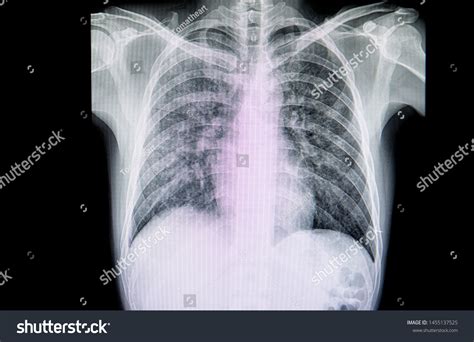

When to See a Doctor

Although the condition is mild, it should not be ignored. You should seek medical attention if you experience difficulty breathing, a persistent high fever, or if your cough worsens significantly. A healthcare provider can perform a physical examination, listen to your lungs, and potentially order a chest X-ray or a lab test to confirm the diagnosis. Early intervention can help manage symptoms more effectively and reduce the time you remain infectious to others.